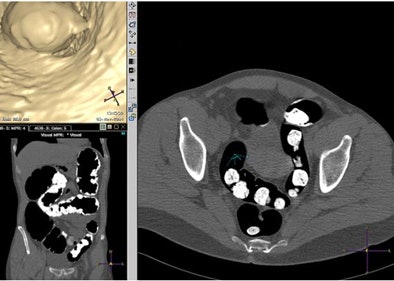

![]() |

| Graphs show subjective image quality scores on per-segment basis. Y-axis shows proportion of segments and x-axis shows preparation groups. Fecal tagging and amount of feces were scored on supine images (for group 1, 66 segments; group 2, 58 segments; group 3, 60 segments; and group 4, 54 segments). Distension and diagnostic readability were scored on supine and prone images (132, 120, 210, and 108 segments, respectively). Group 2 performed significantly poorer regarding amount of residual feces comparison to group 4 (p = 0.04). Image republished with permission of the American Roentgen Ray Society. Jensch S, de Vries AH, Pot D, et al. Image quality and patient acceptance of four regimens with different amounts of mild laxatives for CT colonography. AJR. 2008;191(1):158-167. |